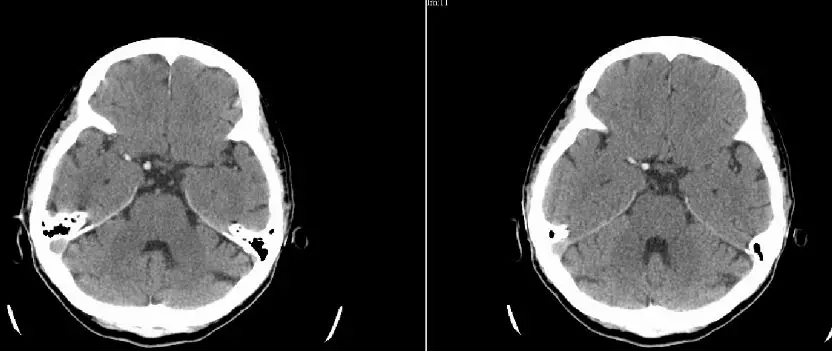

患者在发病80分钟时完成CT平扫,显示右侧颈动脉及大脑中动脉(MCA)M1段、M2段高密度征,提示血栓非常长;ASPECTS评分10分。

患者发病后1小时40分钟行穿刺。血管造影示,右侧颈总动脉(CCA)中部以远未见显影,术前mTICI分级:0级。

侧支循环评估提示右侧大脑后动脉、大脑前动脉(ACA)皮层支发挥部分代偿作用。

大脑后动脉

大脑前动脉